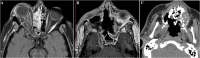

Objective: To determine if there was an increase in the rate of cases presenting with rhino-orbital-cerebral mucormycosis (ROCM) to a tertiary care center during the first wave of the coronavirus disease 2019 (COVID-19) pandemic and the characteristics of the presenting cases. Methods: Retrospective observational study reviewing ROCM cases presenting from March 25 until September 25, 2020. Cases fulfilling the clinical, radiological, and pathological/microbiological criteria for diagnosis with ROCM were included. The number of cases presenting during the designated interval, their COVID-19 status, comorbidities, and clinical presentation were analyzed. The number of cases during the corresponding interval in the previous 3 years was used as reference to detect if there was a recent spike. Results: Of the 12 ROCM cases identified, 5 had a concurrent positive reverse transcription PCR (RT-PCR) test result for severe acute respiratory syndrome coronavirus 2 (SARS-CoV-2), 1 had a prior positive result, and 6 did not have concurrent nor prior positive test results. Nine of the 12 cases had poorly controlled diabetes mellitus, and 2 cases had a hematological malignancy. All cases had orbital invasion, and eight cases had cerebral invasion. The number of cases identified during the interval is much higher than the numbers presenting in the prior 3 years during equivalent intervals (range, one to two cases) than those reported in the literature in different settings in the pre-pandemic era. Conclusions: There is an increased rate of ROCM cases presenting to our center during the first wave of the COVID-19 pandemic. This is a preliminary report, and further studies are needed to corroborate the findings and explain possible underlying links.